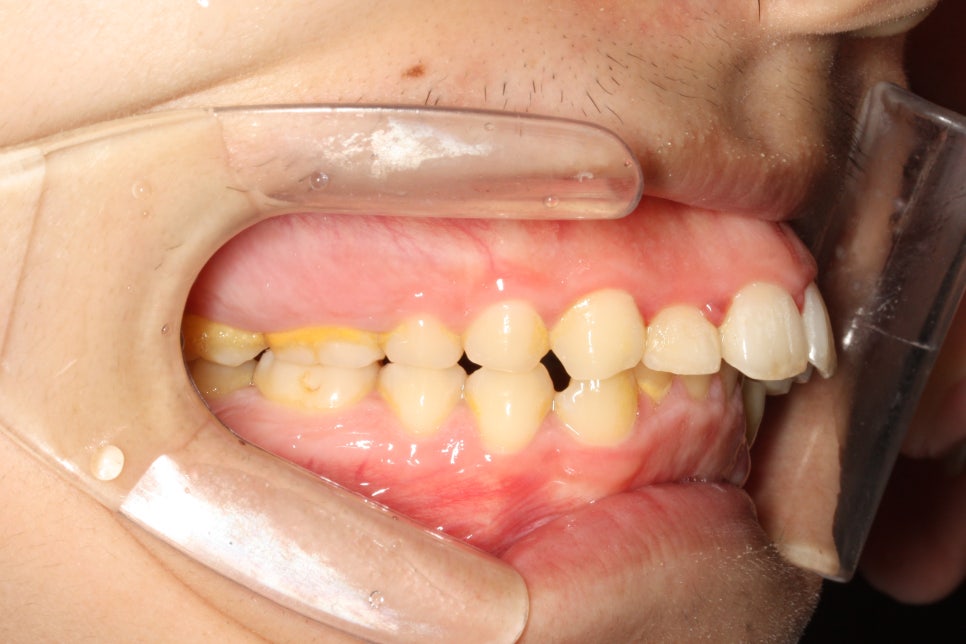

앞니가 많이 돌출되어 있는 환자분이었습니다.

어금니와 송곳니 관계를 보면 발치를 하는 것이 치료를 하는 입장에서 훨씬 편할 수 있는 상태였습니다.

어금니 관계를 보면 1:1 로 만나던 치아가 사이사이 지그재그 들어가는 것이 보이죠?

약 5mm정도 후방이동 된 것으로 보입니다.